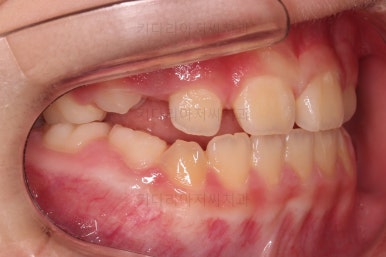

초진 시 입안의 모습입니다.

아래쪽 치열이 전반적으로 윗니보다 앞쪽에 위치한 전형적인 앵글씨 3급 부정교합인데요.

어금니에서부터 앞니까지 아랫니가 윗니보다 앞쪽에 위치하네요.

특히 앞니는 아랫니가 윗니보다 나와있는 "반대교합" 상태였고요.

또한 위아래로 겹침이 없고 떠있는 "개방교합" 상태였어요.

즉, 앵글씨 3급 부정교합 - 반대교합 - 개방교합 등 굉장히 복합적인 교합의 문제를 가진 환자였습니다.